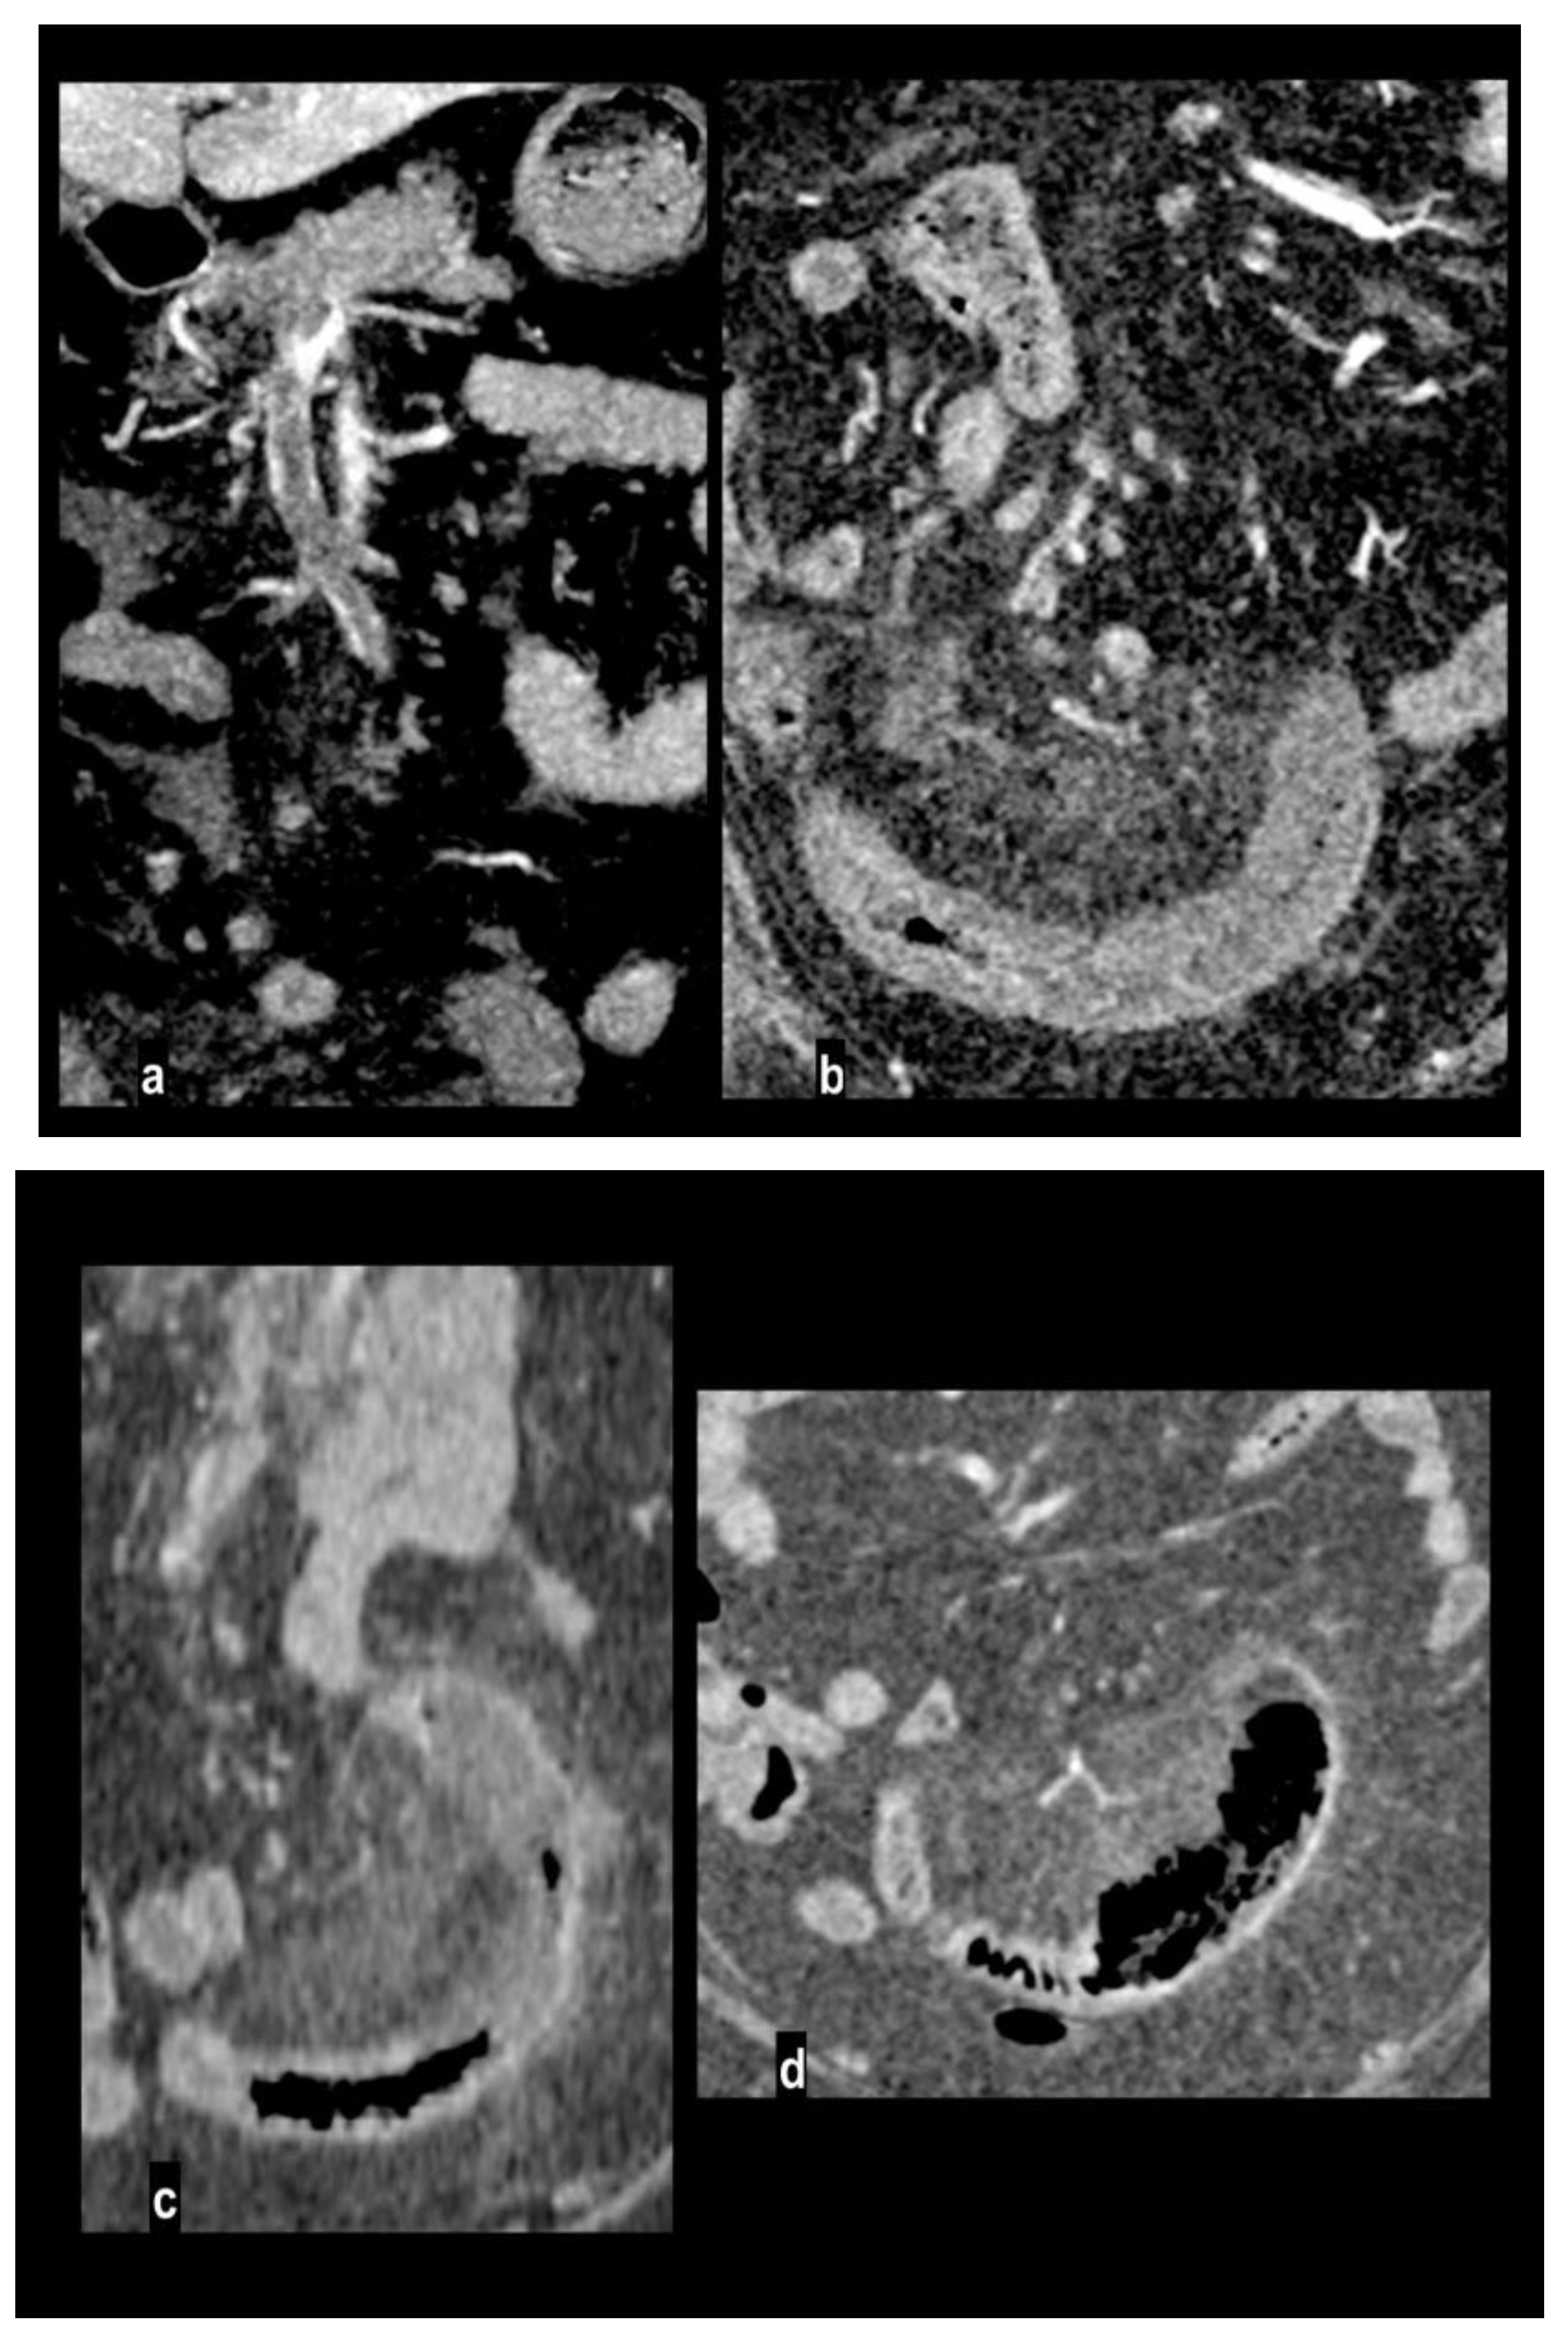

Figure 1. Abdominal pain in a 91-year-old woman with diffuse calcified vascular atheromasia. MIP arterial reconstruction (Figure 1a) showed calcified occlusion of proximal SMA and critical ostial occlusion of the celiac trunk. VR reconstruction (Figure 1b) well depicted an ectasis mesenteric inferior artery and a dilated Riolan artery (arrow), that allowed collateralization of the middle SMA and its branches. MIP reconstructions showed a large caliber of splenic flexure arteries (Figure 1c, arrow) and pancreatico-duodenal arteries (Figure 1d, arrow). However, a watershed territory (ileocaecal junction) didn’t receive appropriate hematic flow and caecum necrosis developed, with hypoenhancing wall thickness and parietal pneumatosis (Figure 1e, coronal MPR; Figure 1f, coronal MIP).